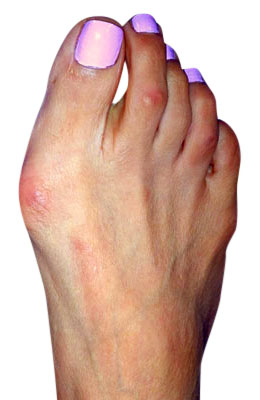

Before

Minimally Invasive Bunion Surgery featuring the CrossRoads miniBunion™ System before

After

Minimally Invasive Bunion Surgery featuring the CrossRoads miniBunion™ System after

Minimally Invasive Bunion Surgery featuring the CrossRoads miniBunion™ System

Eva is a 24-year-old female who had just began working at a job that required high fashion shoes. She was in constant pain but could not take time off work. Our miniBunion™ Minimally Invasive Bunionectomy allowed her to continue to work and be on her foot with full recovery and return to regular shoes by 6 weeks. She had an amazing range of motion, no more bunion pain, and absolutely no visible incision. After picture taken six weeks post-surgery.